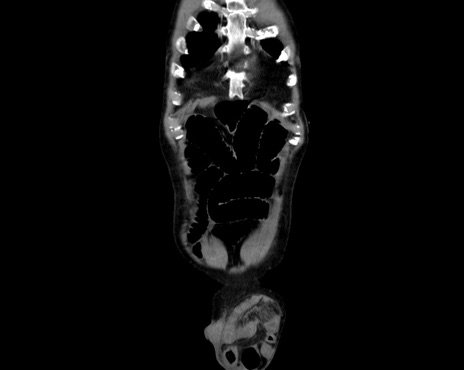

症例26(冠状断像)

【症例】80歳代男性

【主訴】嘔吐

【現病歴】昨晩2回嘔吐あり、今朝になっても嘔吐あり。来院。

【既往歴】胃潰瘍

【身体所見】意識清明、BT 37.6℃、BP 166/95mmHg、HR 100bpm、SpO2 97%、腹部:平坦・軟、腸蠕動音聴取良好、圧痛なし。

【データ】WBC 21900、CRP 1.4